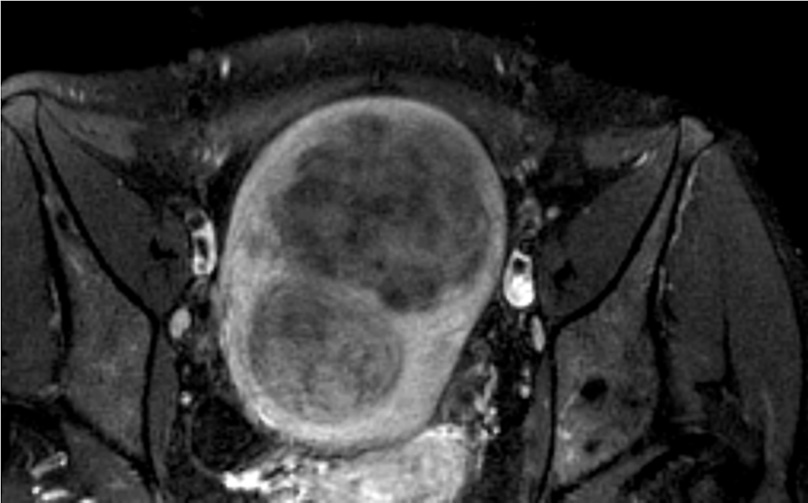

На 2-е сутки госпитализации, по прошествии 18 ч, пациентке выполнено повторное МРТ органов малого таза без контрастирования для выявления эффективности эмболизации, а также выявления нецелевой эмболизации яичников (рис. 12). При сравнении с предоперационной МР-картиной – отчетливо визуализирован описываемый ранее миоматозный узел по передней стенке, повысилась его контурация без признаков значительного изменения размеров; отмечается субтотальное повышение интенсивности сигнала по Т2 от структуры узла. При оценке серий Т1 с подавлением сигнала от жировой ткани структура миоматозного узла представлена диффузным повышением интенсивности сигнала. Строма правого яичника – без изменений. В структуре левого яичника выявляется ранее отсутствующий гиперинтенсивный сигнал в Т1 с подавлением сигнала от жировой ткани диаметром до 6 мм.

Рис. 12. Клинический пример №2. МРТ без контрастирования после проведения ЭМА. / Fig. 12. Clinical case 2. Non-contrast-enhanced MRI after UAE.